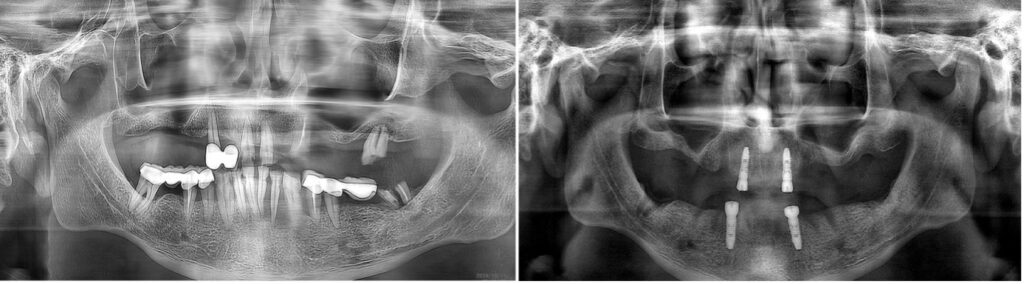

Kontrol edilememiş,HbA1c değeri 10 gibi oldukça yüksek ve riskli bir seviyede olan diyabetli erkek hastamız, mevcut dişlerindeki ileri mobilite, ağrı ve dişeti kanamalarından şikayetle kliniğime başvurdu. Diyabetin bu seviyede olması, cerrahi sonrası kemik-implant birleşmesi (osteointegrasyon) ve enfeksiyon riski açısından en üst düzeyde dikkat gerektiriyordu. Hastanın sistemik tablosuna uyum sağlayacak, iyileşme hızını maksimize edecek bir plan oluşturdum. Bunu yapmasaydım gelişebilecek enfeksiyonar, diş yapalım derken hastanın çok daha hayati problemler yaşamasına sebep olabilirdi.

Yüksek riskli vakalarda cerrahi süreyi kısaltmak ve doku travmasını minimumda tutmak hayati önem taşır. Bu nedenle, tamamen Guided (Rehberli) Cerrahi yolunu seçtim. Dijital planlama sayesinde, milimetrik hassasiyetle çalışarak enfeksiyon riskini ve operasyon sonrası ödemi minimize etmeyi hedefledim. Kesik yok, dikiş yok, enfeksiyon riski az.

Bu vakada, implant yüzeyinin kemikle olan biyolojik etkileşimini en üst seviyeye çıkarmak için UV Active (fotofonksiyonel) implantlar kullandım. UV ışını ile aktive edilen bu implant yüzeyleri, diyabet gibi iyileşmenin yavaş olduğu durumlarda kemik hücrelerinin implanta çok daha hızlı ve güçlü tutunmasını sağlar. Alt ve üst çeneye rehberli cerrahiyle yerleştirdiğim bu implantları, Locator tutucularla destekleyerek hastamız için hem güvenli hem de yeterince stabil bir hareketli protez altyapısı kurdum. Hastayı yaklaşık 5 yıldır takip ediyorum, herhangi bir problemi olmadan dişlerini sağlıkla kullanıyor.